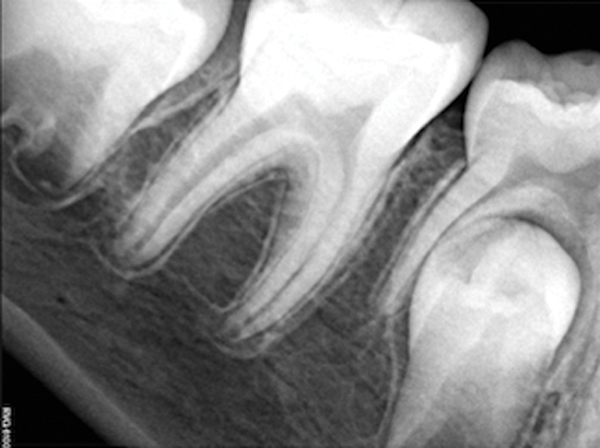

Figure 4. AND Figure 5. Before and after radiographs of bioceramic sealer hydraulically moved with the gutta-percha point. Note that the cold hydraulic technique results in lateral canal “puffs” similar to the warm vertical technique. Courtesy of Dr. Mohammed A. Alharbi.

Pre-mixed BC Sealer is the only pure medical-grade bioceramic product available as a sealer for endodontic obturation. It has the same basic chemical composition as the other pre-mixed bioceramic products, but it is less viscous, which makes its consistency ideal for sealing root canals. It is used with a gutta-percha point, which is impregnated on the surface with a nano particle layer of bioceramic. The gutta-percha is used primarily as the delivery device (plugger) (Figure 1 through Figure 3) to allow hydraulic movement of the sealer into the irregularities of the root canal and accessory canals (Figure 4 and Figure 5).

This sealer solves most, if not all, of the previous problems of traditional sealers. Therefore, a thicker layer of sealer can be used because it is dimensionally stable and does not wash out. The core is used only as a hydraulic pump to move the sealer into place and allow for post space preparation or a pathway for retreatment. In addition and most importantly, the root canal preparation can be conservative and better adapted to restorative needs, since a traditional gutta-percha point (and not a metal plugger) is used to move the filling material. An additional benefit of the system is that there are now gutta-percha points that are impregnated with nano particles of bioceramics, so the sealer bonds not only to the root surface but also to the outer surface of the gutta-percha, eliminating the gap between the two (Figure 19 through Figure 21).